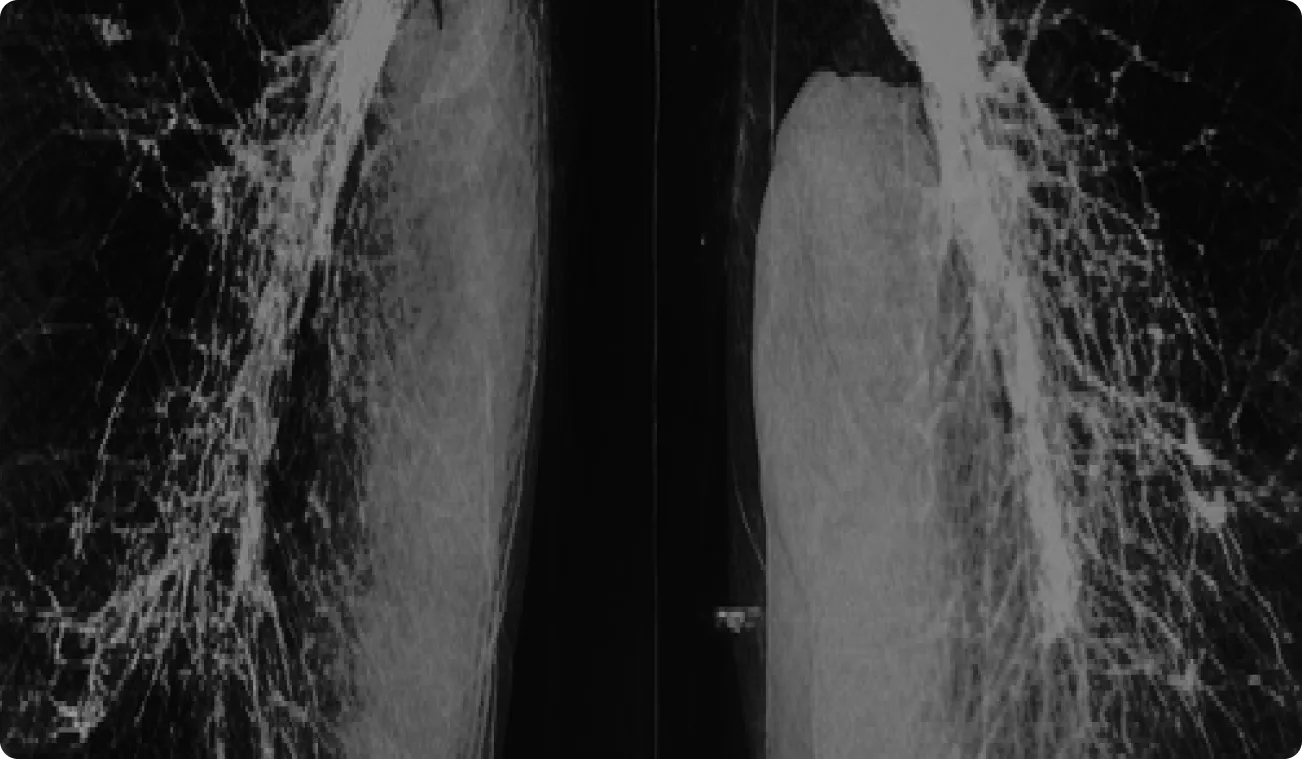

Bellin Health is a distinguished healthcare delivery system renowned for its advanced heart care, and various specialized Health Groups. It’s also the official healthcare provider for the Green Bay Packers, known for exceptional patient care and outcomes.

Bellin faced appointment delays due to incomplete imaging data, requiring extra manual work. Staff spent resources retrieving external reports, especially in Oncology and Orthopedics.

Bellin staff spent 3 hours daily contacting patients, affecting efficiency. With 26,000 annual mammograms, care continuity suffered, causing delays and dissatisfaction, straining physicians.

130% increase in electronic image exchanges